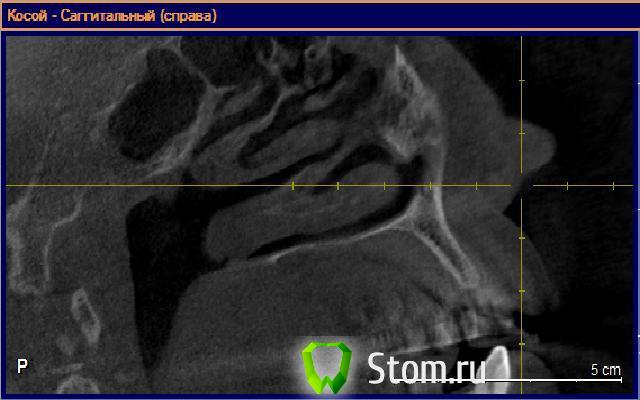

alexandr_spb Опубликовано 6 февраля, 2012 Поделиться Опубликовано 6 февраля, 2012 Добрый день коллеги! составляю план . поправте если что не правильно говорю и делаю.22 зуб - планируется имплантация 3.0 биогоризонт с предварительной аугментацией альвеолярного отростка по методике split control+биоосс+своя костная стружка+мембрана. кт прилагаю. Пациент гарантийный по этой причине костные блоки пока не рассаматриваются. Ссылка на комментарий

Bier Опубликовано 6 февраля, 2012 Автор Поделиться Опубликовано 6 февраля, 2012 мне кажется что целесообразность тех или иных манипуляций должны планироваться исходя в первую очередь из клинической ситуации. На мой взгляд тут нужна предварительная аугментация, хотябы тем же био-осом с мембраной, если владеете методикой ) Но лучше 3D Ссылка на комментарий